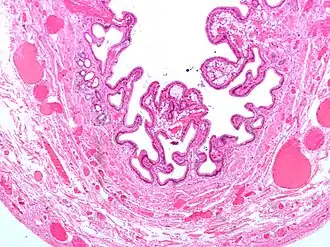

Micrografia da colesterolose da vesícula biliar.

Micrografia da colesterolose da vesícula biliar. -